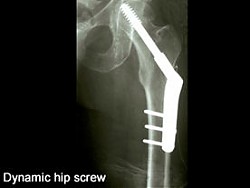

This is precisely what they've done to me to put things right........(tho mine does have 4 lower screws to accommodate my larger arse)